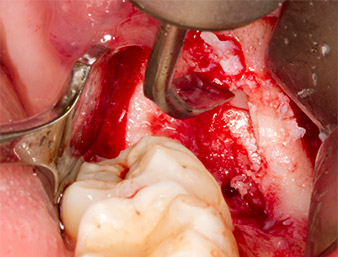

To obtain autogenous material for subsequent wound treatment, healthy bone chips were harvested from the surroundings of the root remnant with a piezo surgical instrument (Piezomed B5) (Fig. 5).

The autogenous tissue was removed with the scraper-shaped section of the working part of the instrument and stored in a physiological saline solution until further use (cf. Fig. 13).

To expose the root remnant with as little trauma as possible to the tissue, a further instrument was used (Piezomed S2) that is primarily indicated for preparing the lateral window in augmentations of the sinus floor. The diamond-coated ball was additionally used to smooth sharp bone edges (Fig. 6 and 7). All the Piezomed attachments were used with the relevant automatic default setting without booster function.